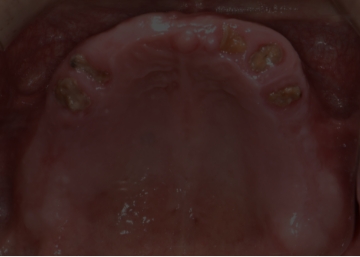

임플란트 : 손 ** 님 (50대)

Before Before

2020.02.30

환자 특징

환자 특징01무치악 상태

환자 특징02수년간 무치악으로 지내심

임플란트가 불가능할것이라

생각하고 내원

위, 아래 6개씩 식립

디지털 풀아치 임플란트